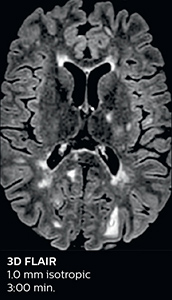

Fast MS protocol with optional sequences

The abbreviated MS protocol for brain is only around 9 minutes, so in case of suspected multiple sclerosis, one or two more advanced sequences may be added, such as PSIR (phase sensitive inversion recovery) or susceptibility-weighted sequences to help us make more confident diagnoses in these inflammatory cases.

In this example, the optional 3D multishot susceptibility weighted sequence with 0.6 mm isotropic voxels is 2 lesions with a central vein sign (arrows) and one lesion with a phase-rim sign (arrowhead). The total scan time, including SmartBrain and axial PD/T2 3mm, is 11:10 min. and is 18:30 min. with the optional 3D PSIR and 3D SWI multishot included.

“In multiple sclerosis patients, we increasingly include a multishot susceptibility sequence [3] in our routine cases, thanks to the shorter scan times. Our abbreviated MS protocol for brain is around 8 to 9 minutes, so we can ask for one or two additional sequences to visualize the central veins, or to get an additional contrast to better depict posterior fossa lesions. In cases of white matter lesions of unknown significance on FLAIR images, for example when we see high signal hyperintensities in the brain, we can add on more advanced sequences such as PSIR (phase sensitive inversion recovery) or susceptibility-weighted sequences to help us in distinguishing between MS and nonspecific or vascular abnormalities in these inflammatory cases.”